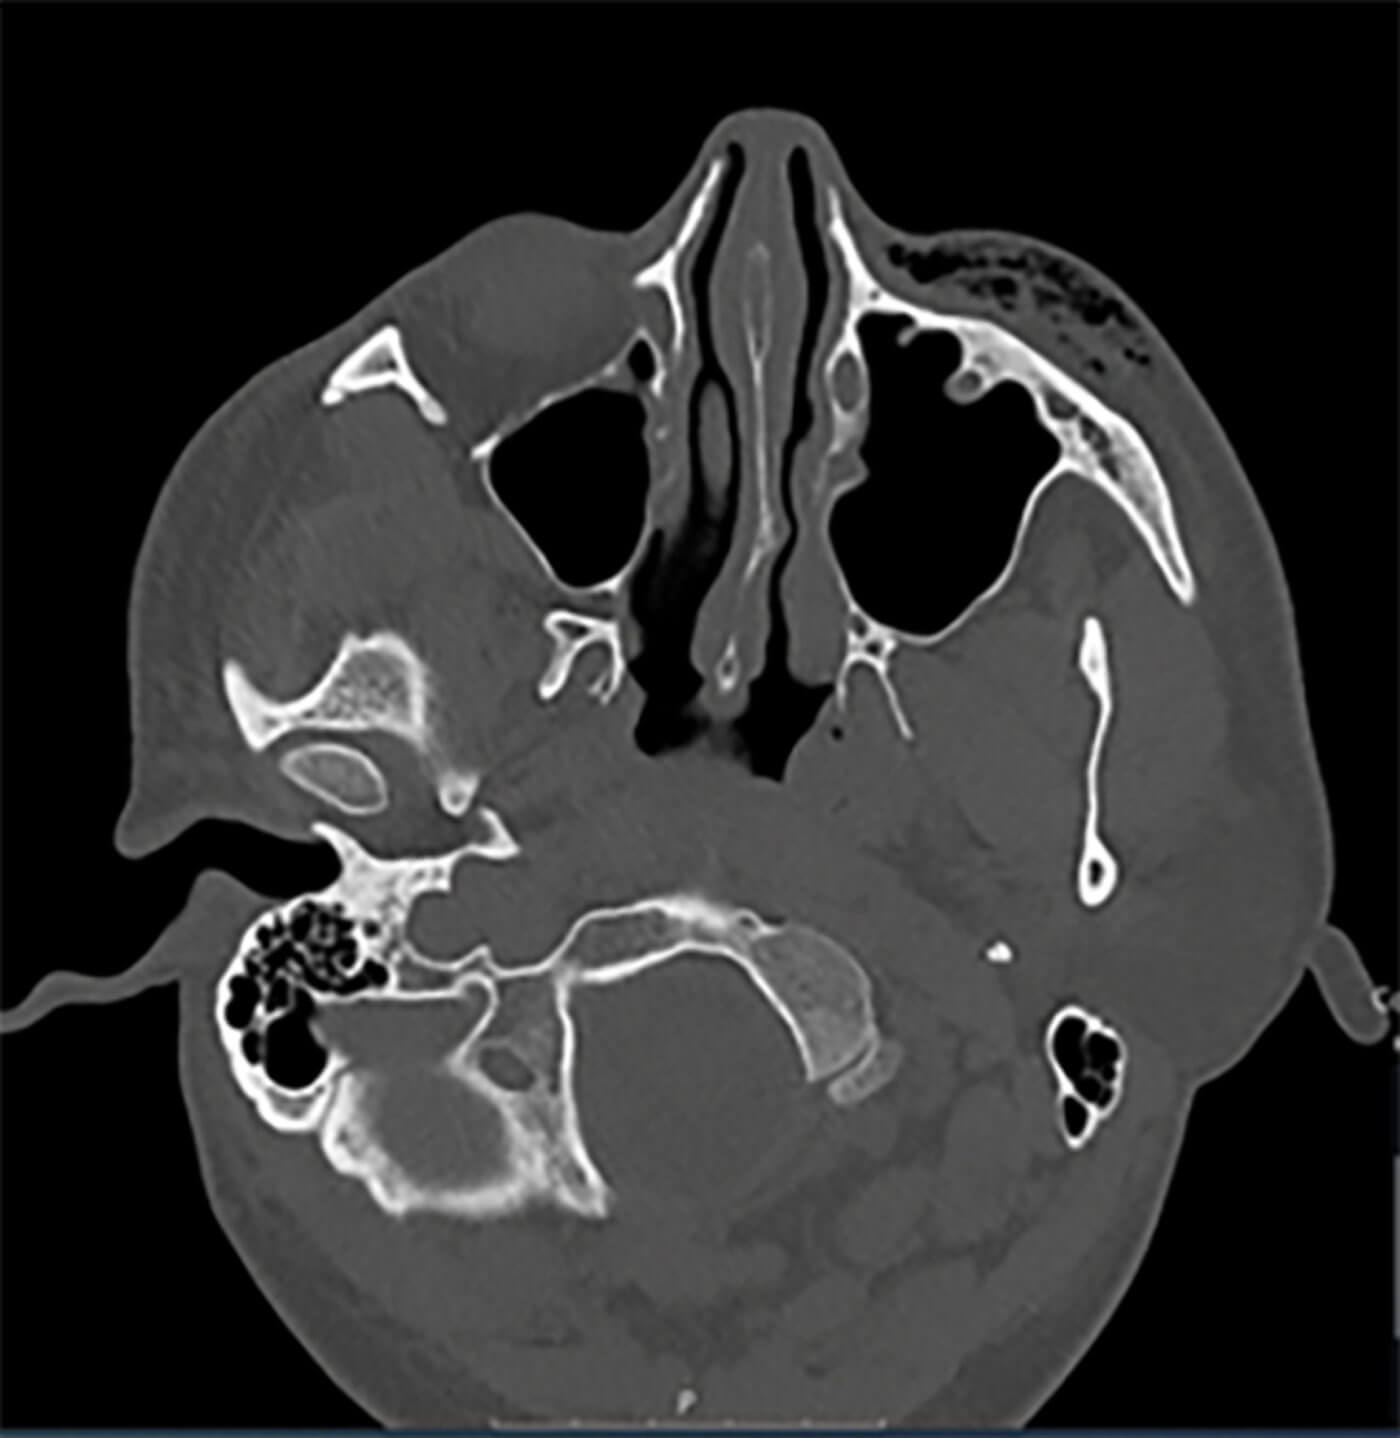

Figure 2: CT orbit demonstrating surgical emphysema in the left orbit.

There is comminuted fracture of the floor of the posterior left orbit and superior maxillary wall.

A computed tomographic (CT) orbits showed surgical emphysema and air in the subcutaneous soft tissues to the left orbit. There was also pneumocephalus in the postseptal fat around the optic nerve. There was a comminuted fracture of the floor of the posterior left orbit and superior maxillary wall (Figure 2). The patient was managed conservatively by his local maxillofacial team, but was subsequently lost to follow-up two months after presentation.